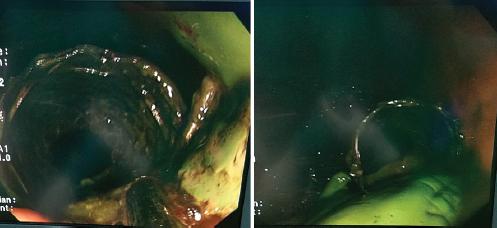

Seis días después es llevada a dicha institución, donde se corrobora la perforación de 5 mm a 38 cm de la arcada dentaria (Fig. 2) y se colocan un clip de Ovesco y una endoprótesis esofágica con cubierta siliconada y mecanismos antimigración.

Figura 2 Endoscopia digestiva alta en la que se visualiza la perforación esofágica momentos antes de colocar un clip de Ovesco.

Se decide en colectivo realizar una exclusión esofágica con suturador mecánico, a nivel del esófago abdominal, previa retirada de las prótesis esofágicas. Durante la endoscopia se diagnostica migración de la prótesis inferior hacia la vertiente gástrica y pérdida total de la cubierta siliconada, la cual se encontraba en el estómago (Fig. 4).

Figura 4 Imágenes de endoscopia digestiva alta en las que se observa la prótesis metálica con el recubrimiento siliconado (color verde) dislocado fuera de ella.